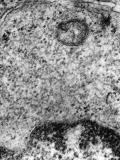

Categories: Mumps virus